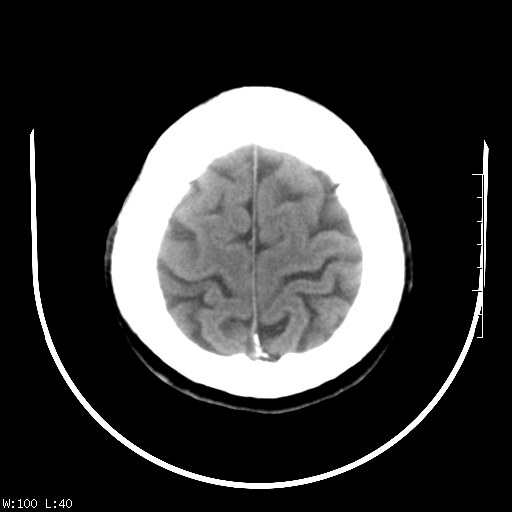

标题: CT22236:男,45,经常头痛。看看脑干正常吗? [打印本页]

标题: CT22236:男,45,经常头痛。看看脑干正常吗?

未见明显异常,建议ct增强或mri检查。

没见异常密度及形态改变啊,我认为是正常的。

颅脑ct轴位平扫颅内未见明确异常。

颅脑ct平扫未见明确异常,必要时mri检查。

颅脑ct平扫未见异常